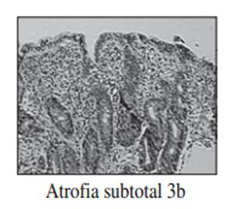

Realizamos una endoscopia digestiva alta y una colonoscopia a la paciente con toma de biopsias, obteniendo el informe de Anatomía patológica.